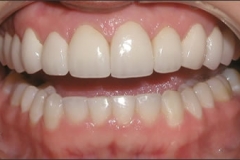

This young patient was self-conscious about the appearance of her short teeth and gummy smile. Through crown lengthening and tooth whitening procedures, we were able to create a beautiful, more mature smile.